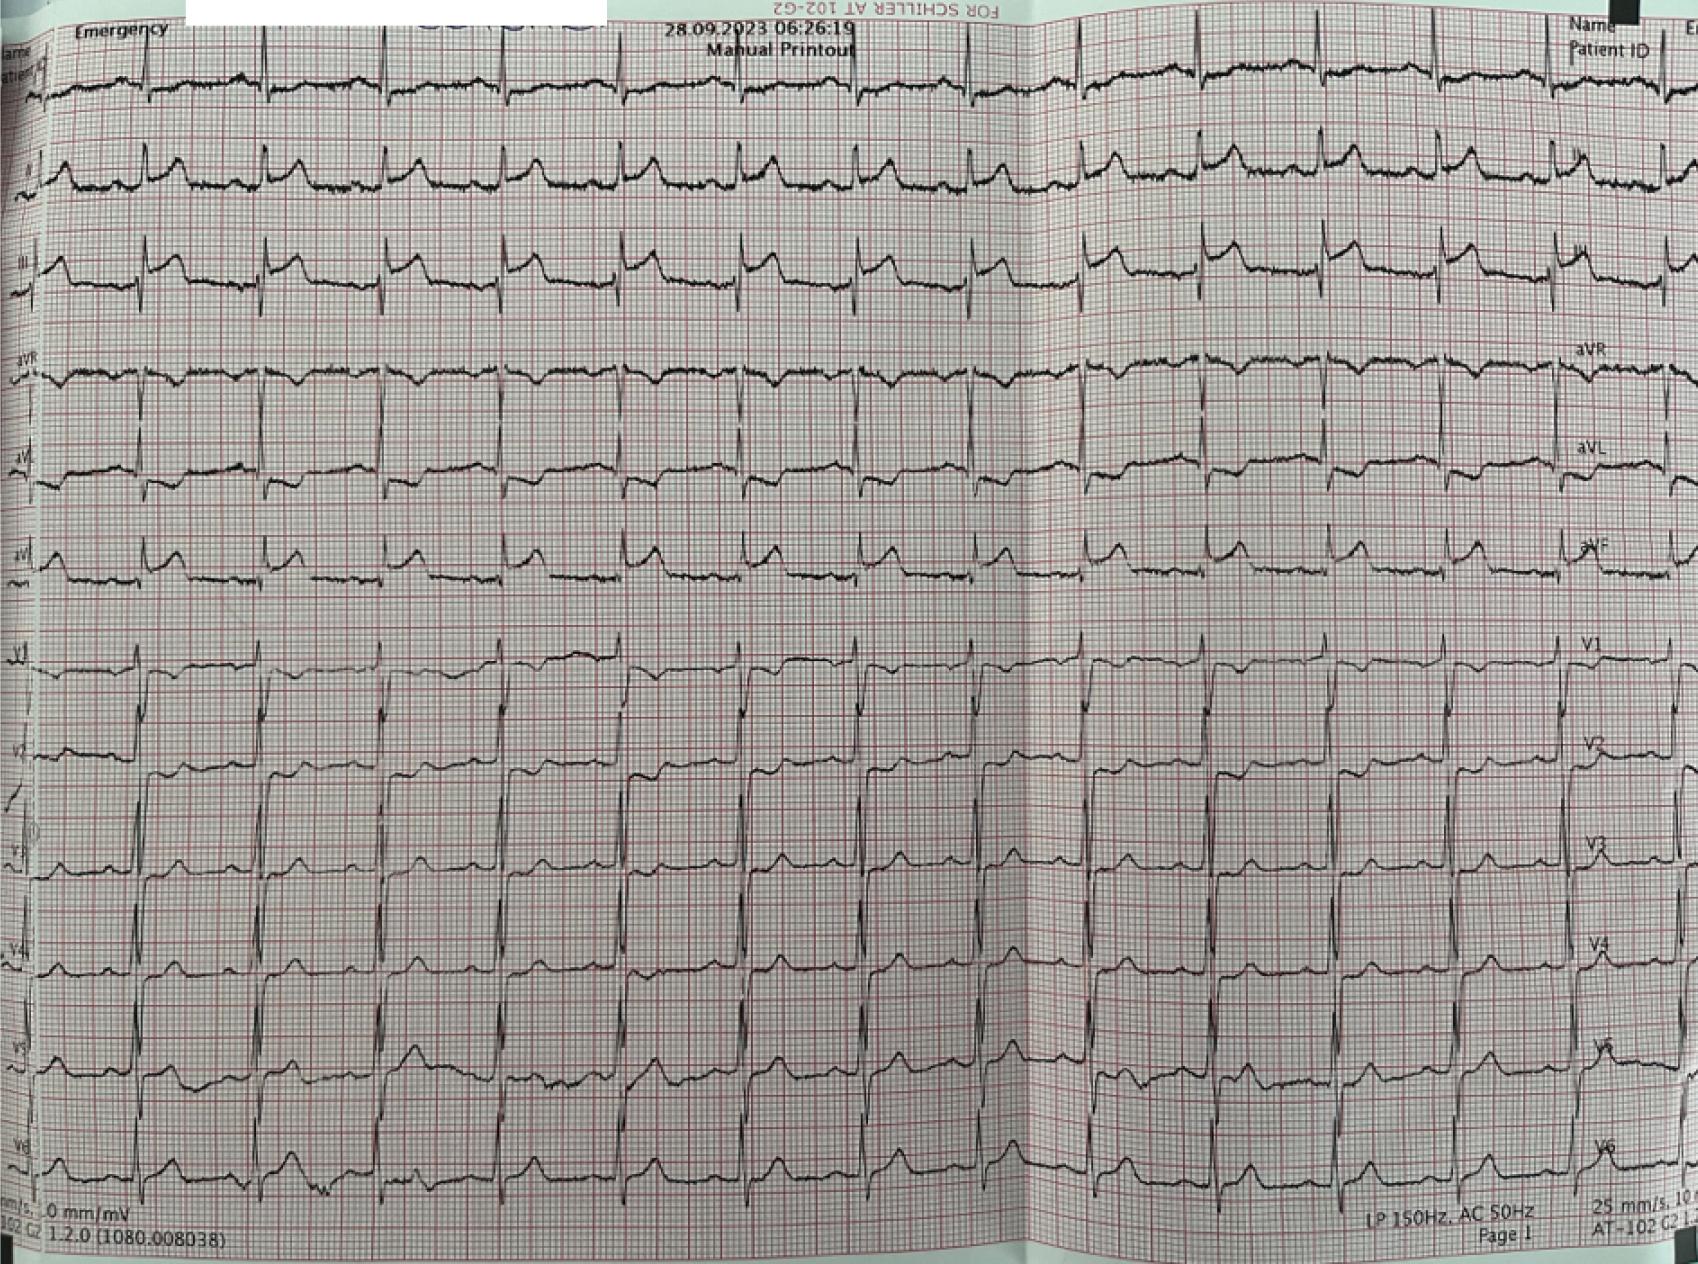

A. Second segment of the right coronary artery occluded by thrombus. B. Bifurcation lesion of the crux cordis after workhorse guide wire crossing. C. Simultaneous kissing stents of the retroposterior branch and posterior descending artery. D. Balloon inflation of the 2 stents. E. Final result showing good peripheral perfusion..